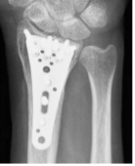

橈骨遠位端骨折に対する鏡視併用手術

橈骨遠位端骨折は頻度の高い骨折の一つで、特に関節内骨折については関節鏡を併用し従来のX線のみでは整復が不十分な関節面の整復を行っています。

術前

術後